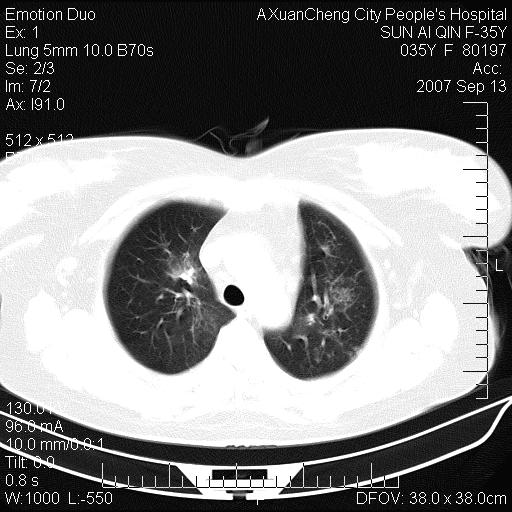

以下是引用天南地北在2007-9-13 13:43:00的发言:[br]考虑双肺、肺门侵润

以下是引用ydx_74在2007-9-13 15:42:00的发言:[br]仅看片,考虑右上肺癌并双肺转移,结合病史,考虑肺门、肺内淋巴侵润

以下是引用同在2007-9-13 15:08:00的发言:[br]支持肺门及双肺侵润.